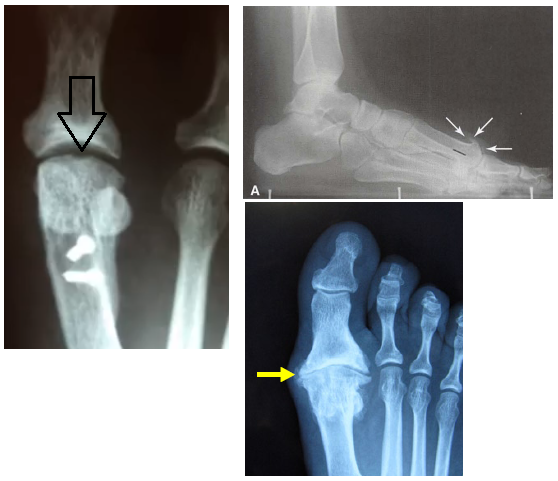

• Quais as principais alterações na radiografia?

A

• Depressão no domo da cabeça do 1° metatarso (artrose inicial)

• Artrose na art. mtfl

• Osteófito dorsal na cabeça do 1° mtt

• Na avaliação radiográfica, qual o 1° sinal a aparecer?